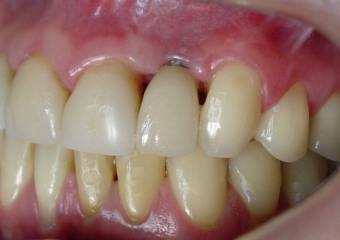

Porção intermediária do implante exposta

Imagem inicial com ausencia do incisivo lateral esquerdo